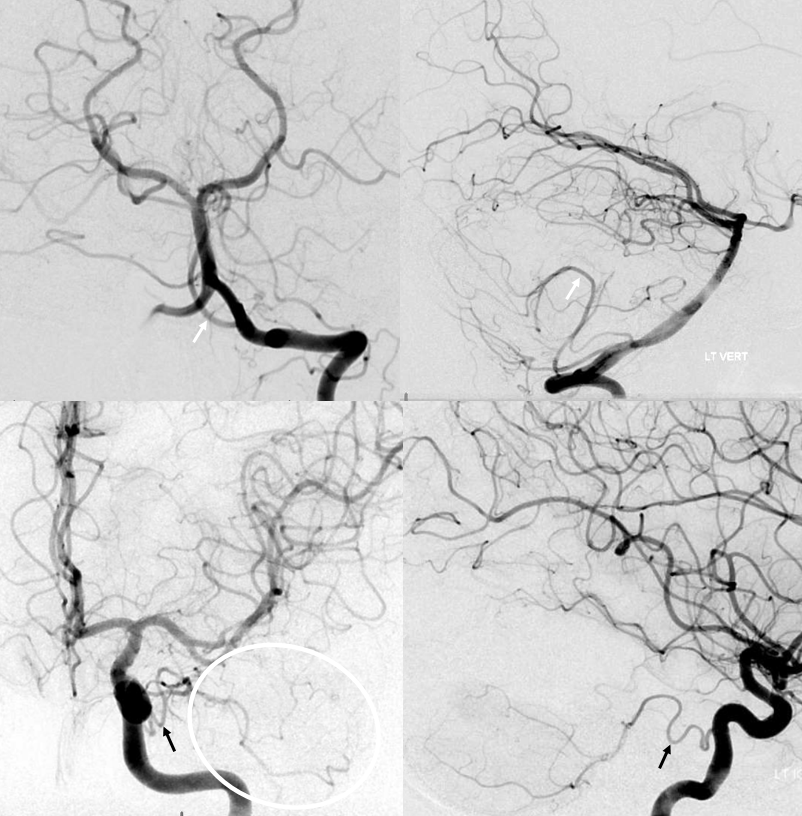

Want more? How about this — see below — the left AICA is hypoplastic. Left PICA (white arrows) supply is limited to vermis. The left SCA is small. How come? There are two possibilities — either the tissue is missing (infarcted, resected, etc), or there is yet another source of supply. The answer is Trigeminal Artery — (black arrows). It again often supplies “AICA territory”. However, insofar as there is really no such thing as “AICA territory” — it being in balance as we keep saying with SCA and PICA — the extent of trigeminal cerebellar supply is as variable as anything else. Here, it is responsible for a big chunk of it (white oval in frontal view), self-evident in lower right lateral view — taking care of both lateral and inferior right hemisphere.